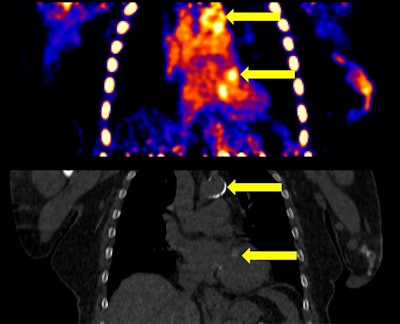

The image on top shows representative vascular calcifications (VCs) in both the aorta and heart in a F-18 NaF static PET image. The increased PET uptake in the VCs is concordant with increased signal and Hounsfield Unit density on the CT image below.The image on top shows representative vascular calcifications (VCs) in both the aorta and heart in a F-18 NaF static PET image. The increased PET uptake in the VCs is concordant with increased signal and Hounsfield Unit density on the CT image below. BMC NephrologyAccording to the results, vascular calcifications (VCs) were visually apparent in all subjects in both cardiac and aortic regions on both PET and CT. Specifically, Ki-Patlak in the aortic VCs increased in all subjects over time (13%; p = 0.005), indicating an increasing rate of aortic mineralization. Increased Ki-Patlak was also seen in cardiac VCs in four of five subjects (p = 0.198).